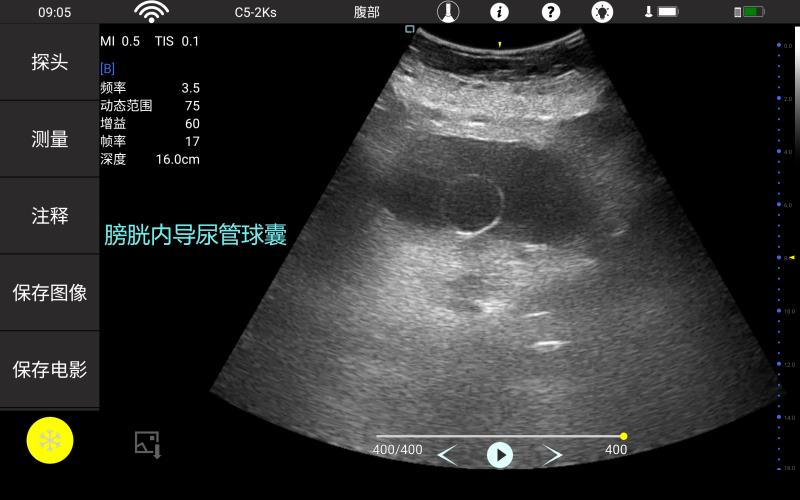

• 腔内

妇产科

泌尿科